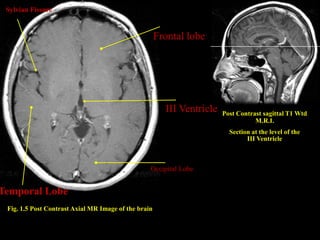

Sylvian Fissure

Frontal lobe

III Ventricle   Post Contrast sagittal T1 Wtd

M.R.I.

Section at the level of the

III Ventricle

Occipital Lobe

Temporal Lobe

Fig. 1.5 Post Contrast Axial MR Image of the brain

Sylvian Fissure Frontal lobe III Ventricle Post Contrast sagittal T1 Wtd M.R.I. Section at the level of the III Ventricle Occipital Lobe Temporal Lobe Fig. 1.5 Post Contrast Axial MR Image of the brain